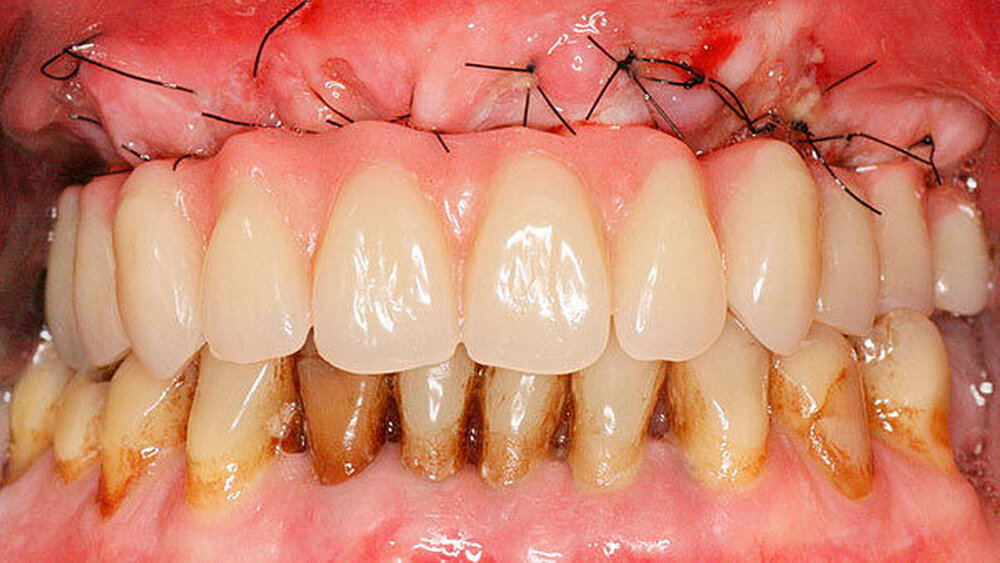

Bei der Sofortversorgung nach dem All-on-4 Konzept (Abbildung 1a-d) werden die frontalen Implantate gerade inseriert und axial belastet, die distalen in der Regel anguliert (Abbildung 2). Durch die Angulation kann ein externer Sinuslift im Oberkiefer umgangen und eine ausreichende Primärstabilisation für eine Sofortversorgung erreicht werden. Im Unterkiefer verhindert das Foramen mentale bei gerader Insertion häufig eine dorsale Positionierung der Implantate. Durch die Angulation der distalen Implantate werden das Belastungspolygon optimiert und ausgeprägte distale Cantilever (Extensionsbrücken) vermieden.

Entscheidend für den Erfolg dieses Konzepts ist die Hygienefähigkeit des Zahnersatzes. Die Basis des Zahnersatzes sollte konvex gestaltet werden und nur linear zum Kieferkamm Kontakt haben (Abbildung 1d). Diese Gestaltung erleichtert eine einfache Mundhygiene mit Interdentalbürsten und Zahnseide. Die Hygienefähigkeit einer All-on-4 Konstruktion ist somit vergleichbar mit einer Stegversorgung. Entscheidend für die Ästhetik ist die präoperative Feststellung der Lippenlachlinie. Diese entscheidet über die Resektionshöhe des Kieferkamms. Die Ästhetik wird bei dieser Versorgungsart ausschließlich über den Zahnersatz erreicht (Abbildung 1d). Die „rote Ästhetik“ kann durch die Verwendung von Prothesenkunststoff individuell und natürlich gestaltet werden. Der Zahnersatz ist bei diesem Konzept okklusal mit den Implantaten verschraubt (Abbildung 1c). Bei Notwendigkeit, zum Beispiel bei Reparaturen, kann dieser durch den Behandelnden leicht ab- genommen werden.